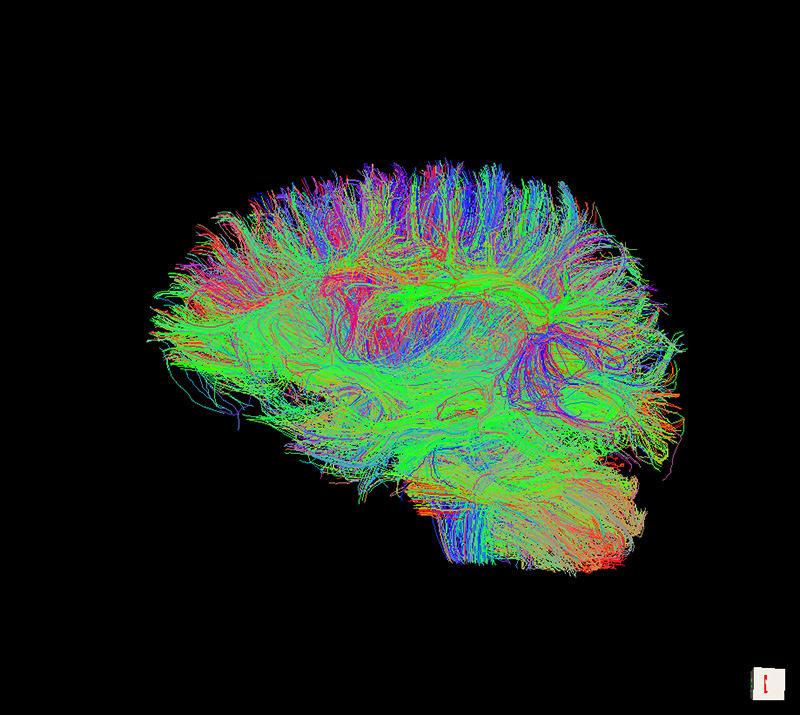

Рис. 3. Пример коннектома головного мозга, рассчитанного у одного из испытуемых (визуализировано с помощью пакета TrackVis).